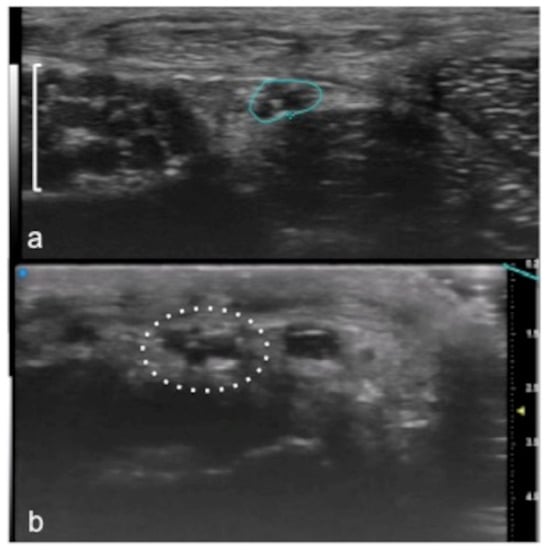

Figure 9.

Visualization of small peripheral nerves using UHFUS. Recurrent branch (line) of the median nerve (square parenthesis) at the level of the thenar eminence in (a). Digital branch (dot circle) of the median nerve at the level of the finger in (b).